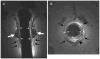

Methods: In this nested case-control study of 68 women with FI (cases; mean age 57 years) and 68 age-matched controls from a population-based cohort in Olmsted County, MN, pelvic floor anatomy and motion during voluntary contraction and defecation were assessed by magnetic resonance imaging. Obstetric events and bowel habits were recorded.

Results: By multivariable analysis, internal sphincter injury (cases-28%, controls-6%; odds ratio (OR): 8.8; 95% confidence interval (CI): 2.3-34) and reduced perineal descent during defecation (cases-2.6 ± 0.2 cm, controls-3.1 ± 0.2 cm; OR: 1.7; 95% CI: 1.2-2.4) increased FI risk, but external sphincter injury (cases-25%, controls-4%; P<0.005) was not independently predictive. Puborectalis injury was associated (P<0.05) with impaired anorectal motion during squeeze, but was not independently associated with FI. Grades 3-4 episiotomy (OR: 3.9; 95% CI: 1.4-11) but not other obstetric events increased the risk for pelvic floor injury. Heavy smoking (≥ 20 pack-years) was associated (P=0.052) with external sphincter atrophy.

Conclusions: State-of-the-art imaging techniques reveal pelvic floor injury or abnormal anorectal motion in a minority of community women with FI. Internal sphincter injury and reduced perineal descent during defecation are independent risk factors for FI. In addition to grades 3-4 episiotomy, smoking may be a potentially preventable, risk factor for pelvic floor injury.